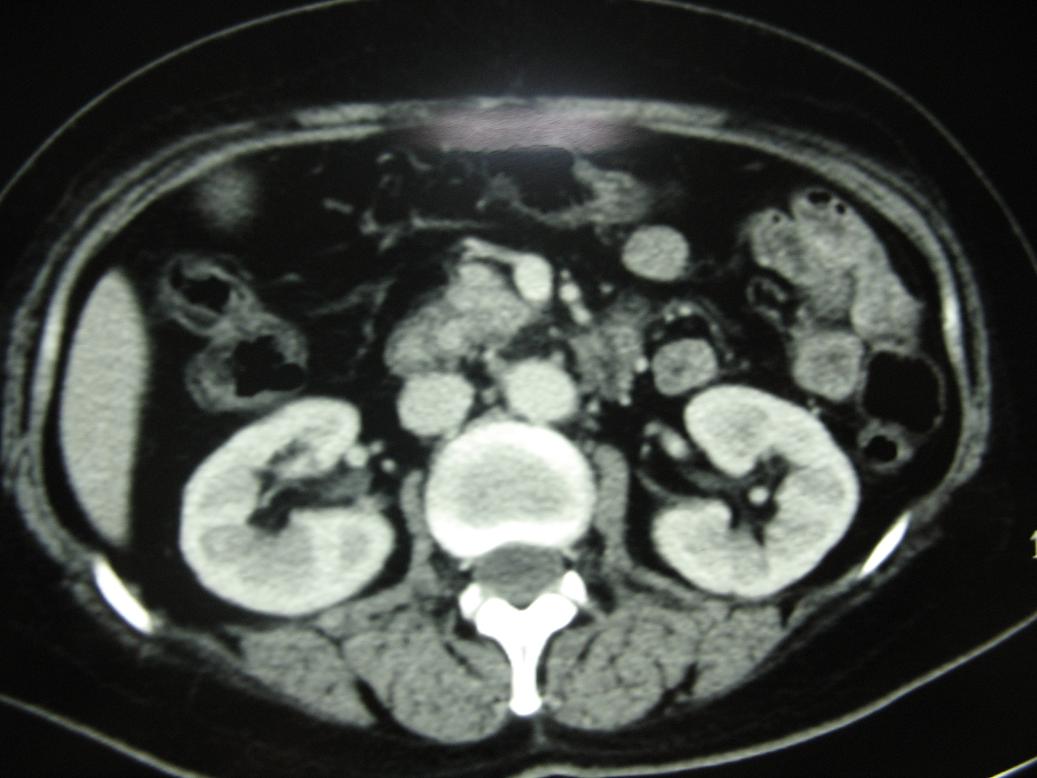

标题: CT17151:女 53岁 腹痛数月余 轻微黄疸 [打印本页]

女 53岁 腹痛数月余 轻微黄疸

1)考虑胰头癌。2)胆囊炎。

壶腹周围占位(钩突ca?)

胰腺钩突mt

支持胰腺钩突ca伴胆系梗阻,胆囊炎

考虑 胰头癌可能性大。